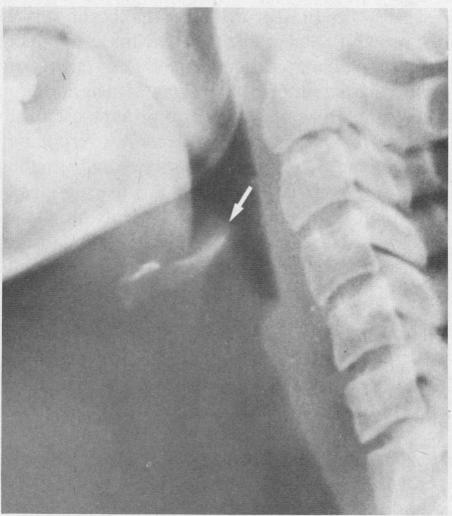

Epiglottitis in an immunosuppressed host.

[Acute epiglottitis].

Tracheotomy in acute supraglottitis (epiglottitis): the treatment of choice.

Haemophilus epiglottitis.

Airway intervention in croup and epiglottitis--update '78.

Acute infectious epiglottitis in adults.

Acute epiglottitis. Review of 55 cases and suggested protocol.

Epiglottitis--individualized management with steroids.

Acute epiglottitis in adults.

Acute epiglottitis. A surgical emergency.

The safety of intubation in croup and epiglottitis: an eight-year follow-up.